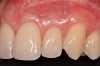

Various procedures to correct deficient gingival contours have been well documented in the dental literature.1,2 Increasing zones of attached gingiva using palatal donor tissue and the free gingival grafting procedure was introduced by Björn almost a half century ago.3 Using palatal donor tissue in the form of a free soft-tissue autograft for root-coverage procedures was reported by Miller.4 Additional procedures were reported using lateral5 or coronal repositioning6-8 of the adjacent attached gingiva via a pedicle flap or the coronal repositioning of previously grafted tissue.9,10 Miller also reported on gingival grafts placed over root surfaces to correct areas of deep-wide gingival recession.11 Further surgical advancements led to the use of subepithelial connective tissue from the palate to obtain root coverage.12-14 Figure 1 shows the pretreatment view of a mandibular central incisor, and Figure 2 depicts the post-treatment view of the site treated with a subepithelial connective tissue graft harvested from the patient’s palatal tissues.